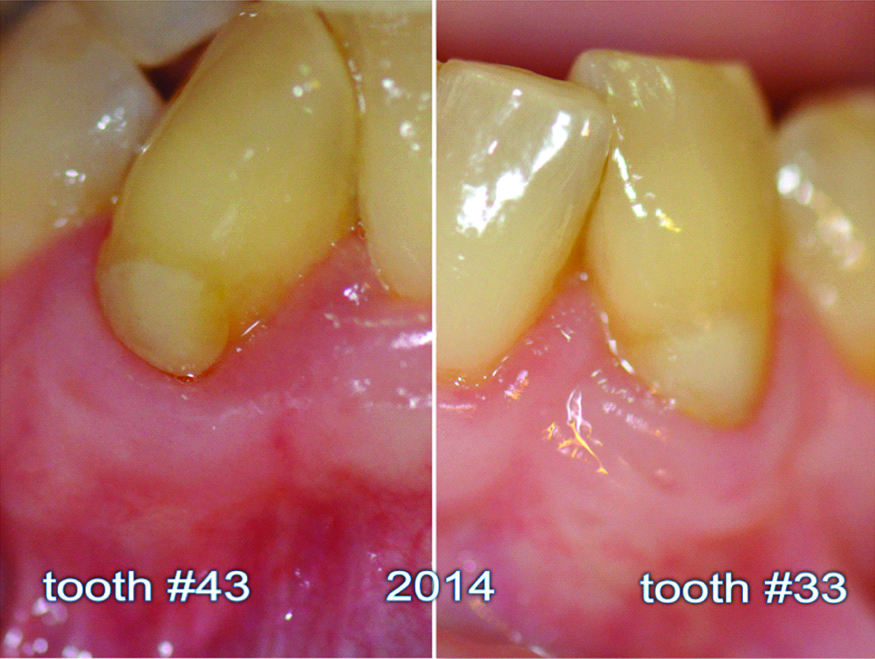

During the follow-up period, which lasted for 18 years, no adverse significant changes were noted over time. Instead, the root coverage and keratinised tissue increased over time [Table/Fig-7,8,9,10,11 and 12].

Follow-up images of teeth #33 and #43 in 2014.